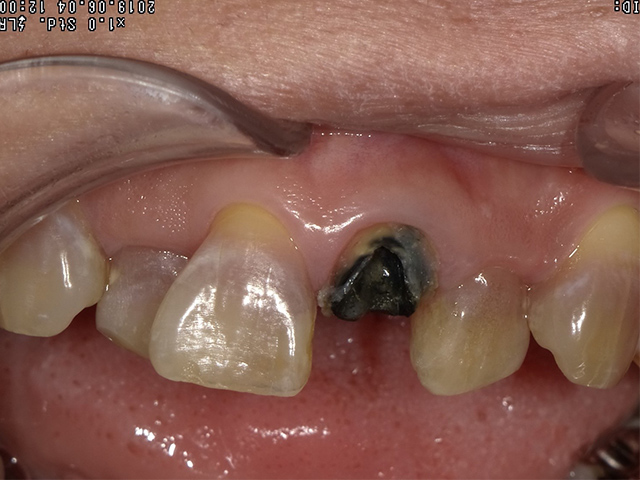

虫歯が歯の根元まで深く進んでしまった場合。

歯が折れて、その折れた線が歯ぐきの奥深くまで達している場合。

被せ物をつけるのに十分な歯の量が足りないけれど、歯の根っこ自体はしっかりしている場合。

BEFORE |

引っ張り上げた際についてきた歯周靭帯を切除して、歯質を高さ・厚み共に2ミリ以上確保することが出来ました。